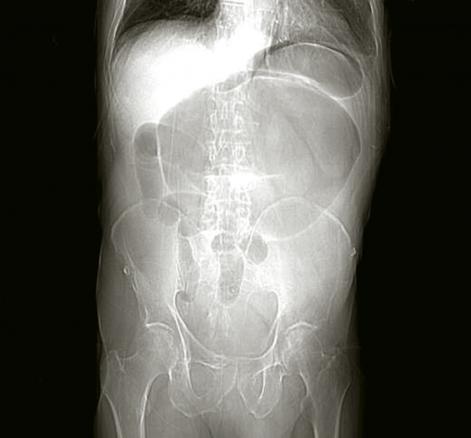

Volvulus du cæcum sur un abdomen sans préparation

2. Volvulus du cæcum sur un abdomen sans préparation